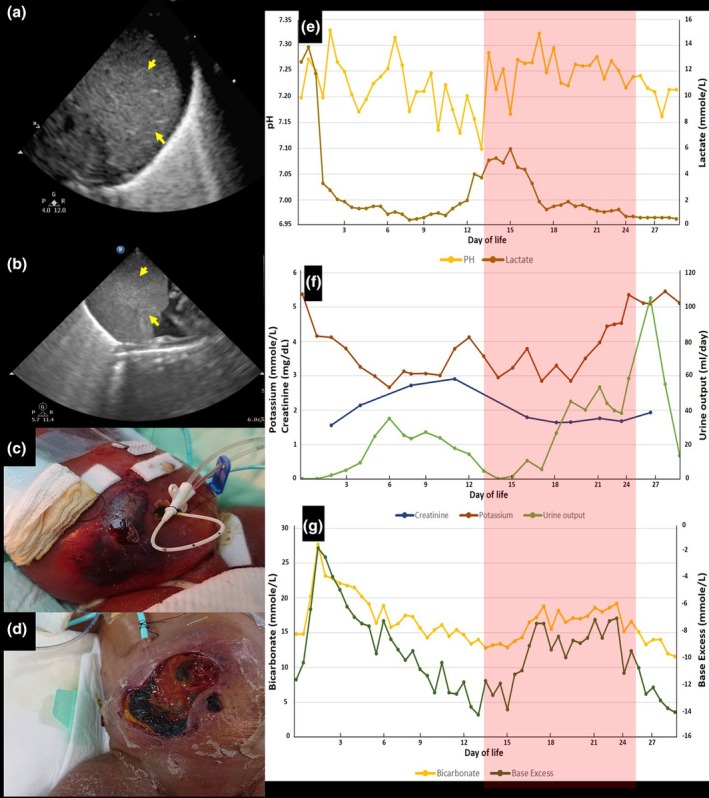

Peritoneal dialysis in an ELBW infant after resolution of hemoperitoneum: Challenges with peritonitis and cellulitis.